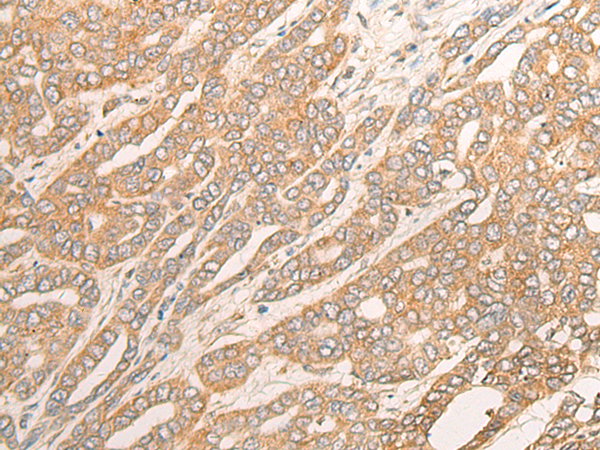

DCTD |

Full name: |

IHC Positive control: |

Human liver cancer; |